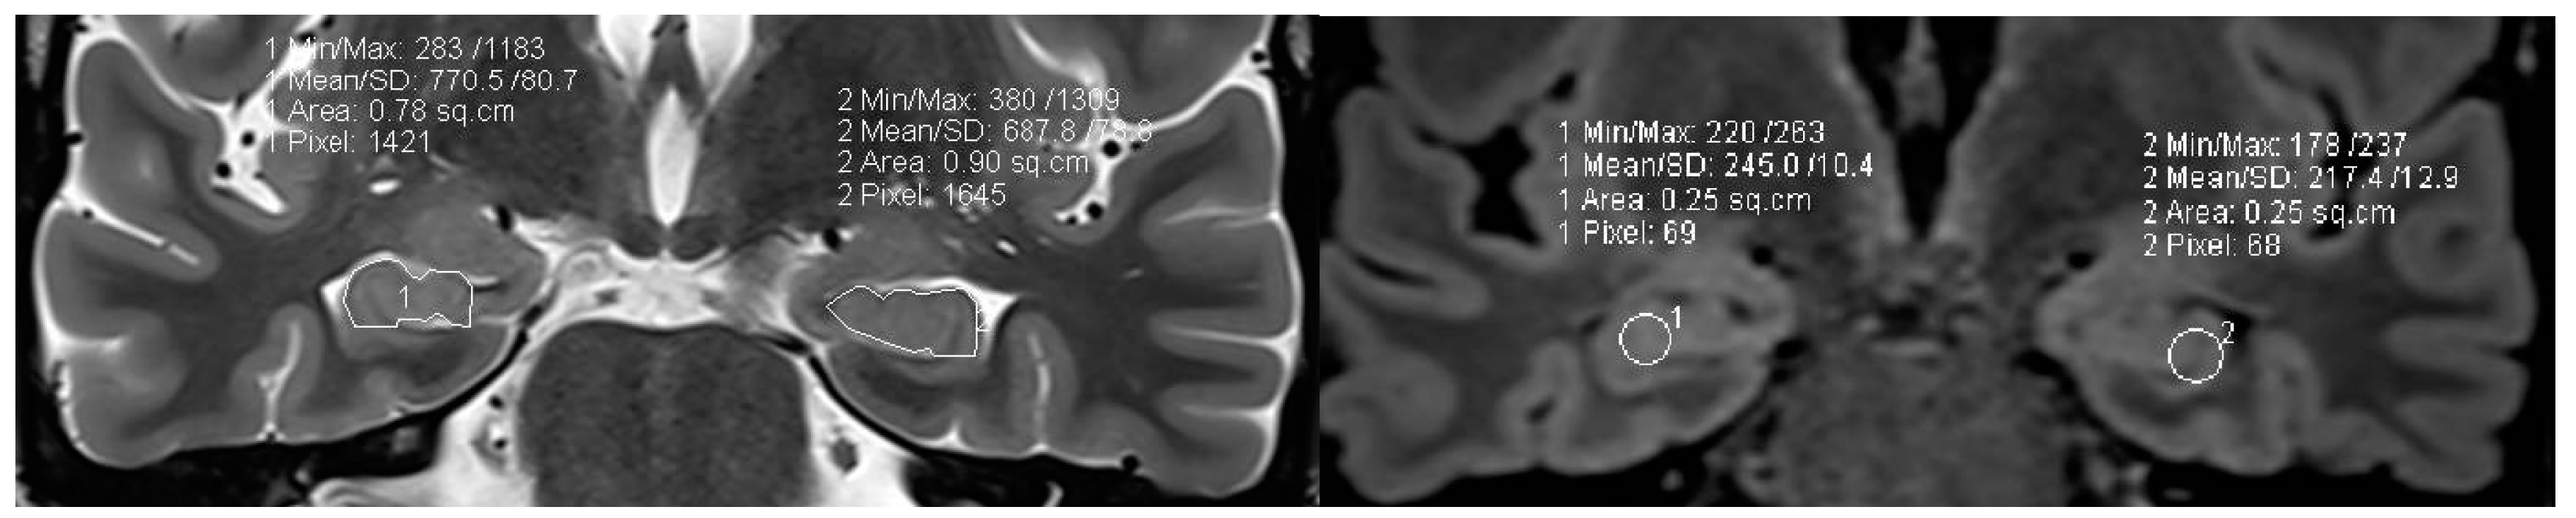

4.8. Postprocessing by 3D Surface Rendering Technique to Improve Comprehension of Superficially Located Lesions